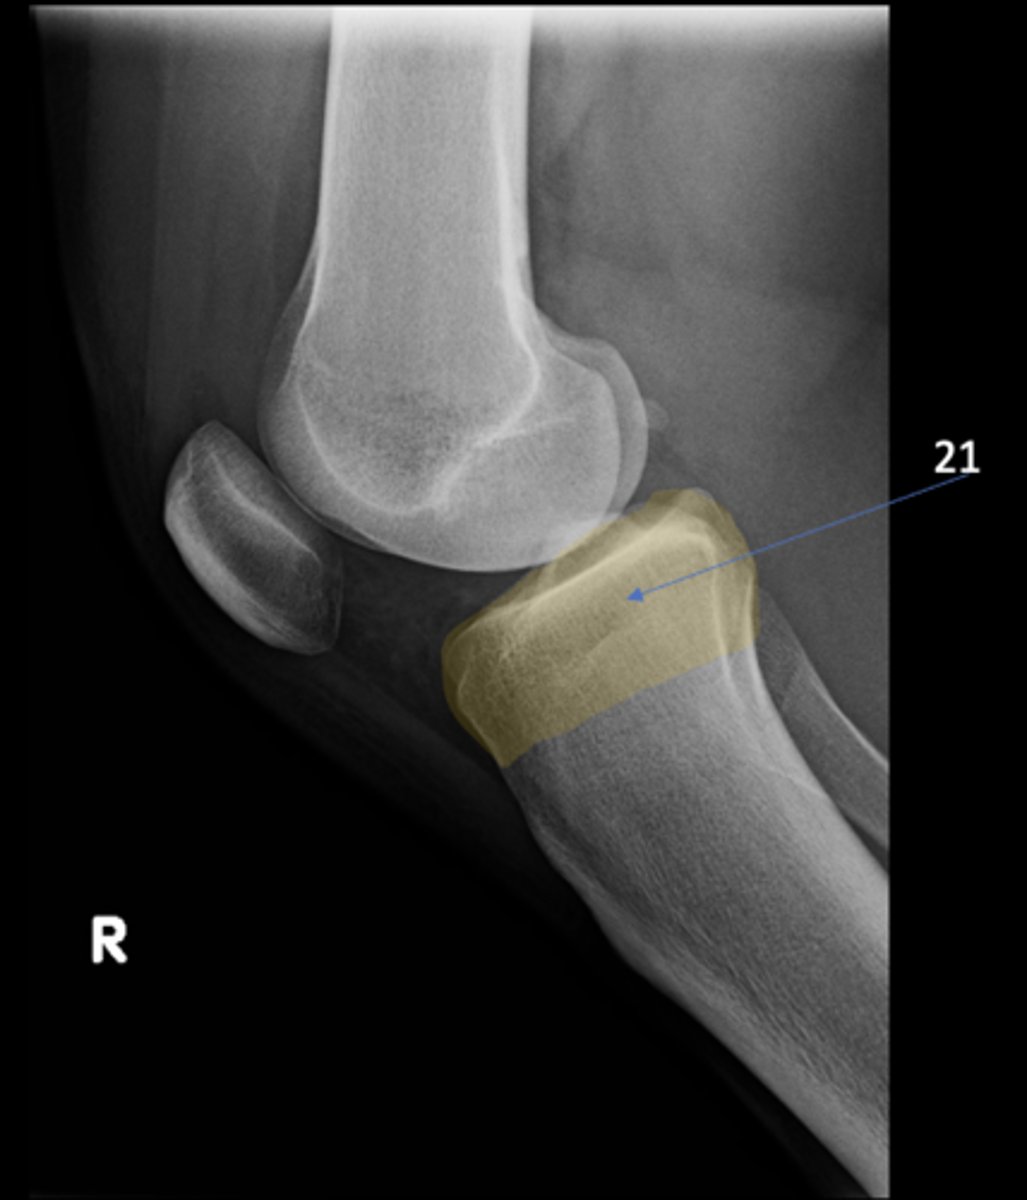

Right lateral knee

View?

<p>View?</p>

68

70

New cards

Both tibial condyles

ID 21

<p>ID 21</p>